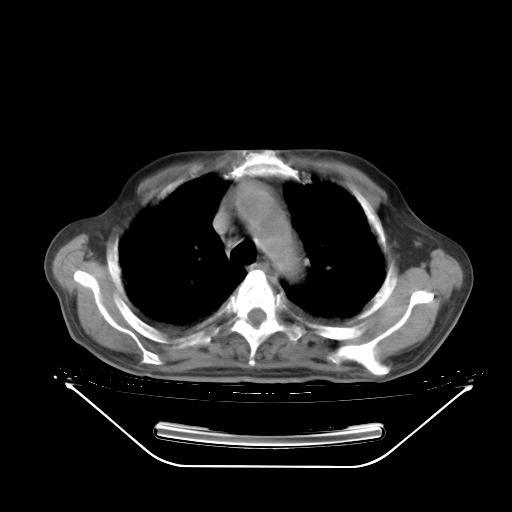

今天复查肺部CT,发现双肺广泛磨玻璃样改变。所以我把3月19日和5月9日相隔50天的肺部CT上传。请大家会诊。

2009年3月19日肺部CT片。

5月9日肺部CT(在4月27日齐鲁医院肺部CT描述部分肺组织磨玻璃样改变,12天后肺组织广泛磨玻璃样改变)